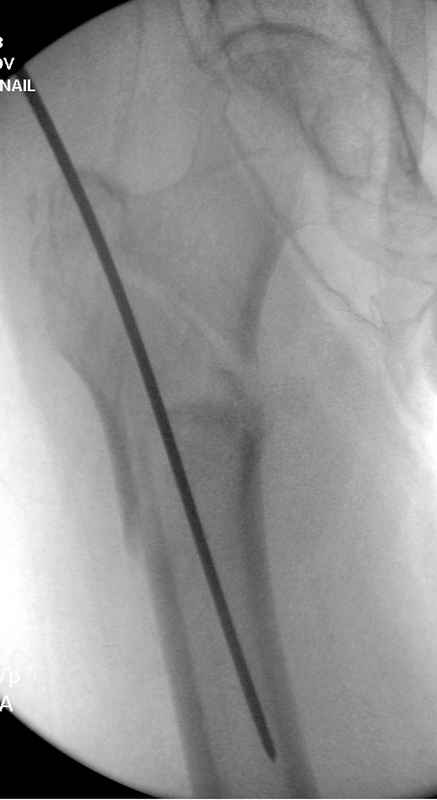

Здесь пара случаев фиксации похожих переломов:

первый высокоэнергетическая травма 36 лет

Djoldas Kuldjanov, M.D.

Department of Orthopedic Surgery

St. Louis University